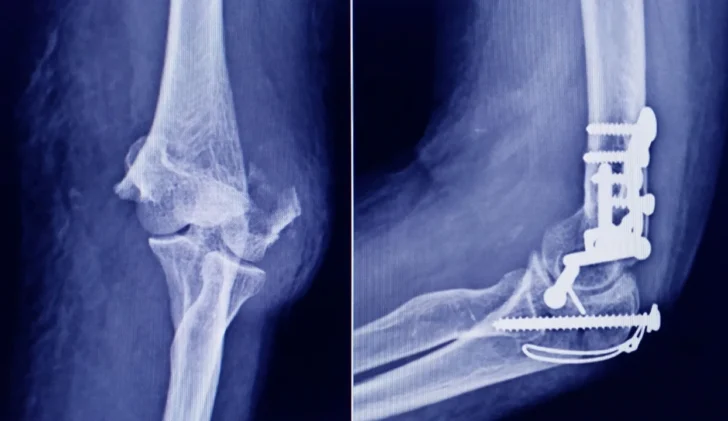

La Administración Nacional de Medicamentos, Alimentos y Tecnología Médica (ANMAT) advirtió a la población por un tornillo utilizado en cirugías traumatológicas debido a que es falso, por lo que su uso representa riesgo para la salud del paciente al que se lo implante.

Se trata de un tornillo utilizado en cirugías traumatológicas que fue detectado durante una inspección de control de mercado realizada en una ortopedia ubicada en la ciudad de San Miguel de Tucumán.

Las autoridades de la ANMAT dieron a conocer las características del producto para su advertencia: STRYKER 10 mm X 28 mm – BIOABSORBABLE – ACL INTERFERENCE SCREW – REF 234-010-067 – LOT 90905.